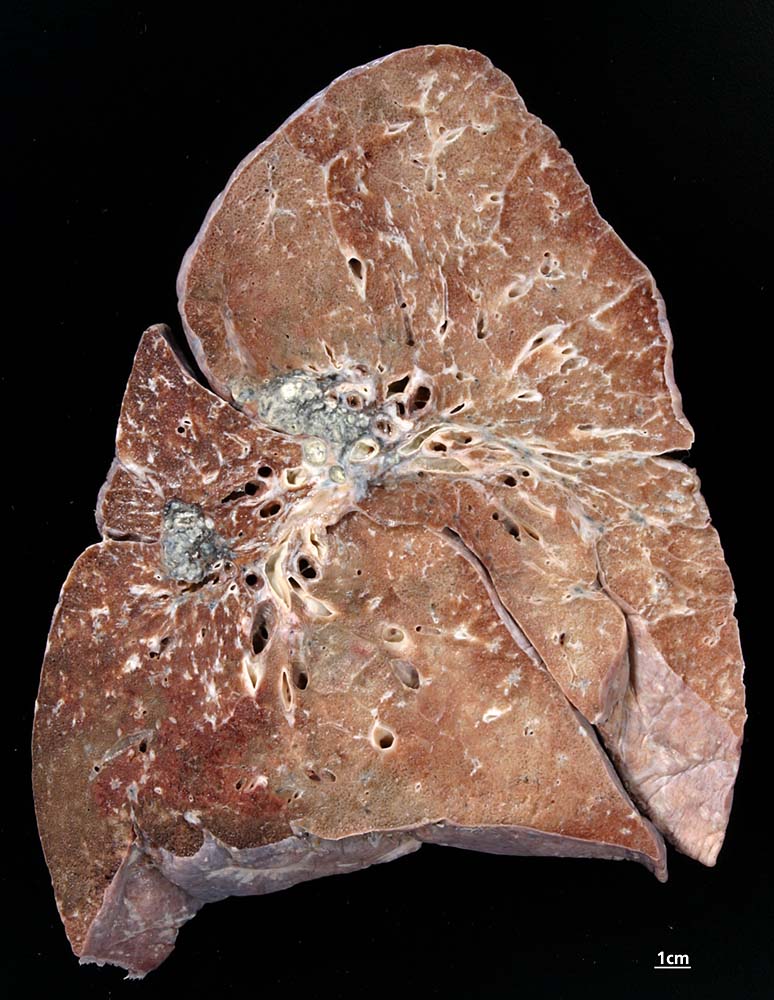

Die Morphologie der Erkrankung ist stadienabhängig. Initial findet sich eine lymphozytenreiche Alveolitis mit wenigen kleinen Granulomen. Die Granulome bestehen aus Aggregaten epitheloider Histiozyten teilweise mit Beteiligung von mehrkernigen Riesenzellen. Im Verlauf entwickeln sich zellreiche Granulome entlang der bronchovaskulären Bündel und der Interalveolarsepten, welche später konfluieren und vernarben. Die Riesenzellen können Asteroidkörperchen (sternförmige Kristalle) oder Schaumannkörperchen (lamelläre Verkalkungen) enthalten. Ein Teil der Patienten entwickelt eine irreversible Lungenfibrose.

• Zahlreiche produktive, nicht nekrotisierende Granulome aus dickleibigen Epitheloidzellen, Riesenzellen vom Langhanstyp und Lymphozyten.

• Ausgeprägte Fibrosierung der Granulome.

• Herdförmige Vernarbung des Lungenparenchyms.

• Bevorzugte Lokalisation der Granulome im Bereich von Bronchiolen und Pulmonalarterienästen. Das sollte der Kliniker dem Pathologen mitteilen: